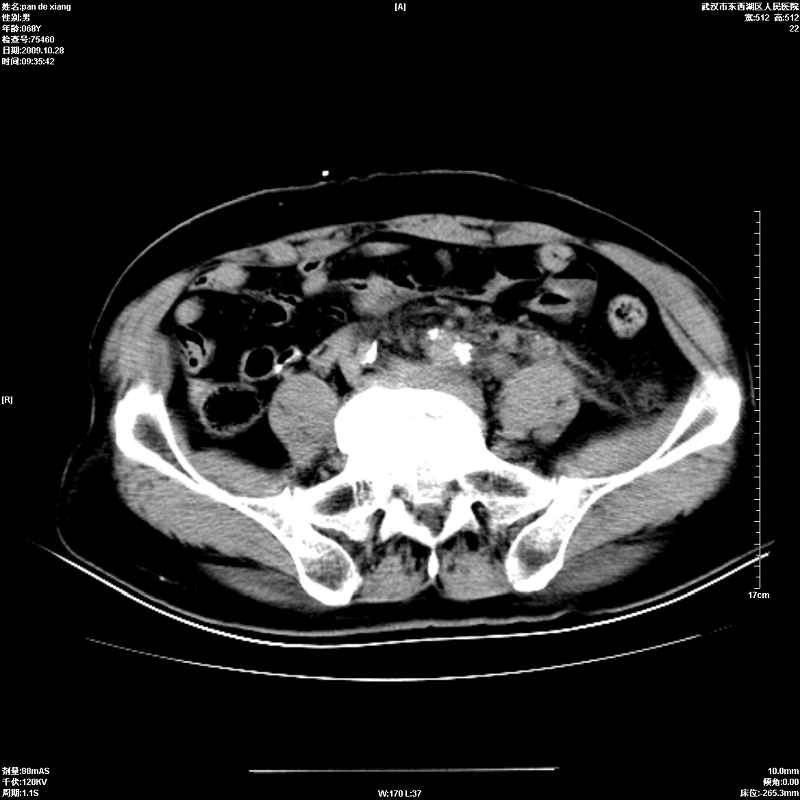

以下是引用杀毒软件在2009-10-28 20:41:00的发言:[br]结合临床考虑---白血病双肾改变或淋巴瘤。

以下是引用zxl51642在2009-10-29 9:59:00的发言:[br]结合临床“单克隆免疫球蛋白血症”,考虑双肾为继发损害并肾功能不全(尿中大量igg及少量iga、igm等大分子免疫球蛋白滤出所致继发损害),椎前软组织肿块为髓外造血。与浆细胞瘤有区别,平扫时有战友说的很清楚。